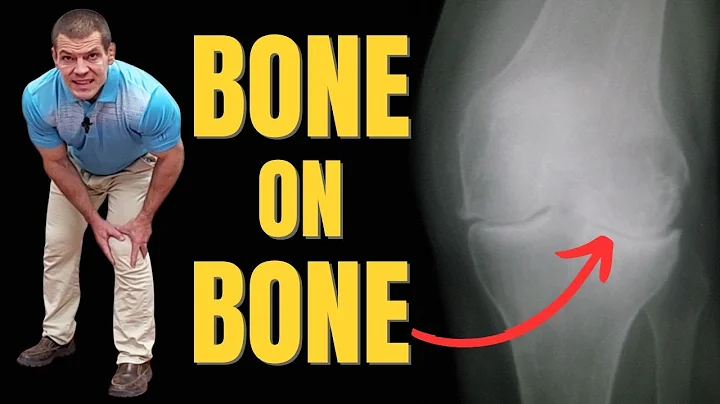

3 Exercises To Relieve Bone On Bone Knees

It's possible to find RELIEF ✓ Have you been told your knees are bone on bone? Sounds scary right? Actually, it may not be as ...